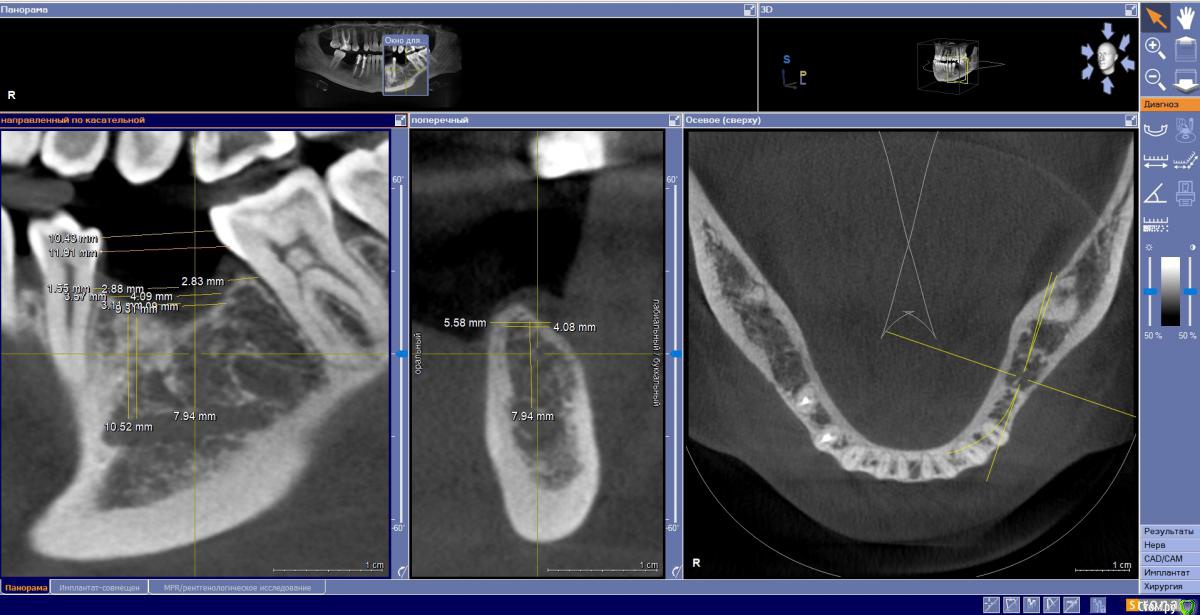

Fin Опубликовано 29 июля, 2020 Поделиться Опубликовано 29 июля, 2020 Здравствуйте коллеги. У пациента отсутствуют зуб 3.5 и 3.6. и высоко расположенный канал тройничного нерва. Что бы вы сделали в данном случае? Наращивать ширину? Ставить ССТ? Ссылка на комментарий

annda Опубликовано 3 августа, 2020 Поделиться Опубликовано 3 августа, 2020 (изменено) Стоял до этих имплантатов суперлайн коротыш 7мм,одиночка.Заколебались с раскруткой винта,ходила каждый месяц.Плюнула,решили выкрутить,переставить на эти.КТ после удаления. Изменено 3 августа, 2020 пользователем annda 1 Ссылка на комментарий

annda Опубликовано 4 августа, 2020 Поделиться Опубликовано 4 августа, 2020 Что-то с загрузкой пошло не так,извините.Контроль после постановки и контроль с абатментами(через 3 месяца) Ссылка на комментарий